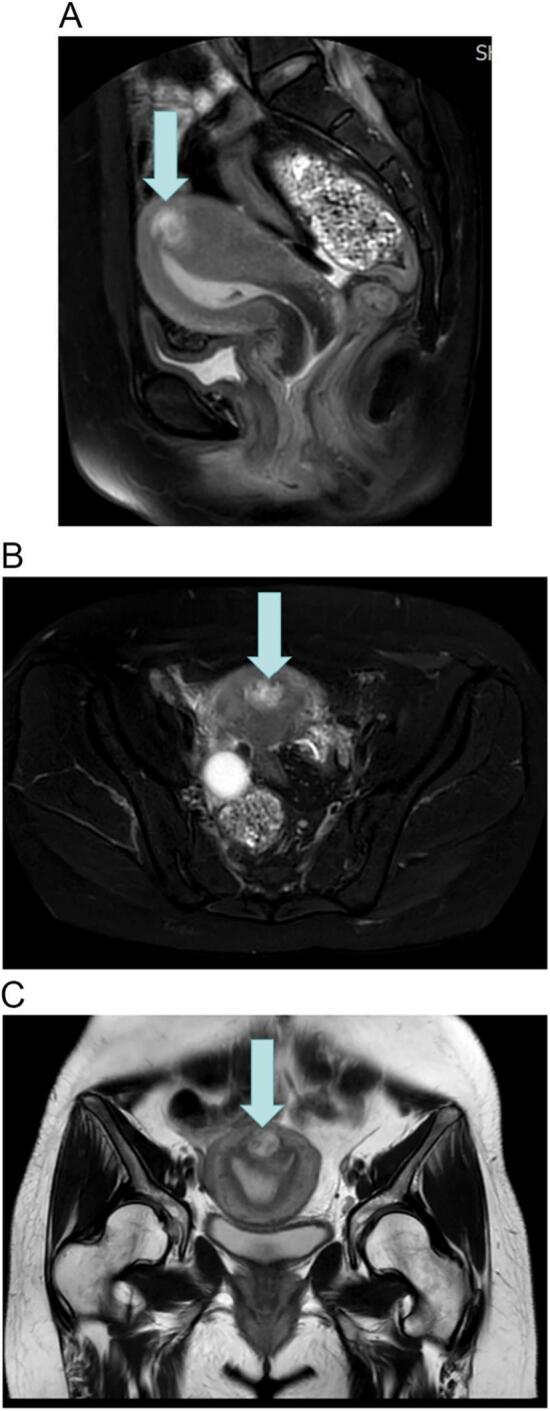

Persistence of ectopic pregnancy after intramural ectopic pregnancy surgery: A case report.

We report a case of IMP after embryo transfer in a 38-year-old woman. The patient developed persistent ectopic pregnancy after combined hysteroscopic and laparoscopic surgery. Intramuscular injection of methotrexate did not have a significant effect, and transabdominal ultrasound-guided in situ injection of methotrexate at the site of the lesion was performed with a significant impact.

This case emphasizes the complexity of the treatment of IMP. Surgery alone may not allow complete excision of the lesion, and residual chorionic tissue may invade the muscular vessels; this case emphasizes the importance of postoperative drug therapy.

IMP invades the myometrium in a widely spreading manner, and methotrexate injection in situ at the site of the lesion after conservative surgery may become an efficacious treatment modality.